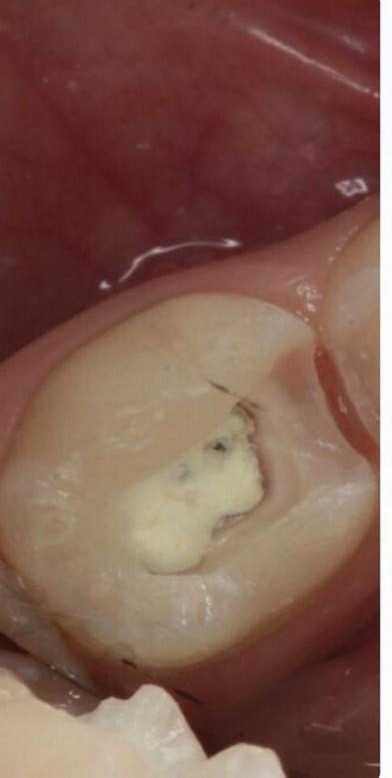

4 работы в портфолио